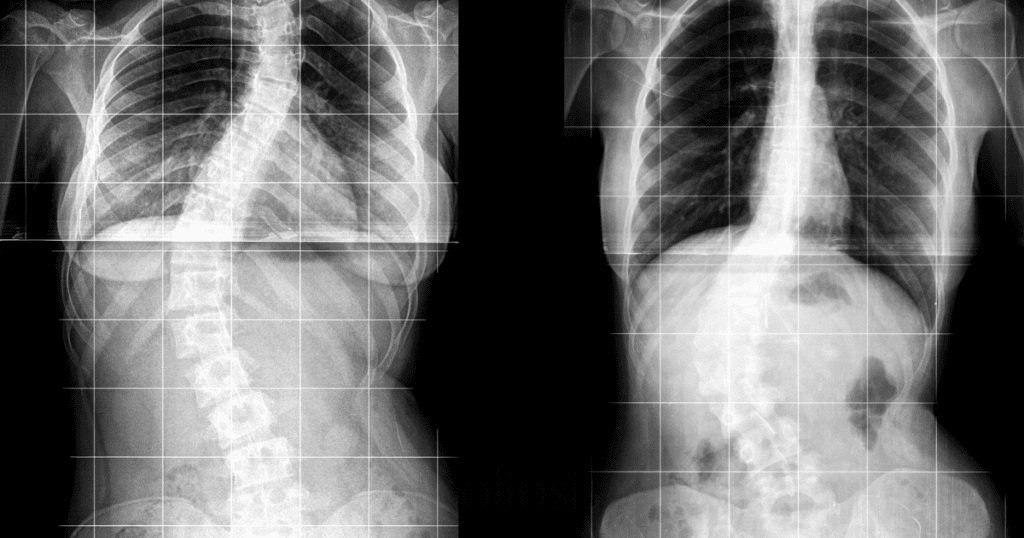

Imagine a life free from the discomfort and limitations of scoliosis—advanced scoliosis treatment offers non-surgical solutions designed to improve spinal alignment and enhance your quality of life. These treatments focus on reducing spinal curvature, alleviating pain, and improving posture through specialized therapies such as bracing, targeted exercises, and innovative corrective techniques. Scoliosis treatment can help manage symptoms, prevent progression, and enhance mobility, reducing the need for invasive procedures. By addressing the underlying issues associated with scoliosis, these therapies empower you to move with greater ease and confidence in your daily life.

- A visible curve in the spine